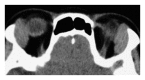

Orbital IgG4-related disease, which can occur in adults of any age, is characterized by IgG4-positive lymphoplasmacytic infiltrations in ocular adnexal tissues. The signs and symptoms include chronic noninflammatory lid swelling and proptosis. Patients often have a history of allergic disease and elevated serum levels of IgG4 and IgE as well as hypergammaglobulinemia. Orbital IgG4-related disease must be differentiated from idiopathic orbital inflammation and ocular adnexal marginal zone B-cell lymphoma to ensure appropriate and effective treatment. Systemic steroid therapy decreases the size of the lesions, but relapse often occurs when systemic steroid therapy is discontinued.